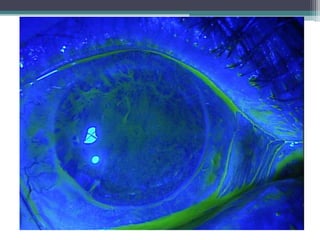

Stem cell deficiency

• 65 Y.O man with a history of alkaline burn.

• Presented initially 5 years ago with a melted,

perforated cornea.

• Underwent PK, achieved 20/30 was stable until

1 month ago. Presented with visual acuity of

20/200, partial stem cell failure

• Underwent selective epithelial debridment with

prokera, achieved 20/70 and improving.

• Avoided a stem cell transplant